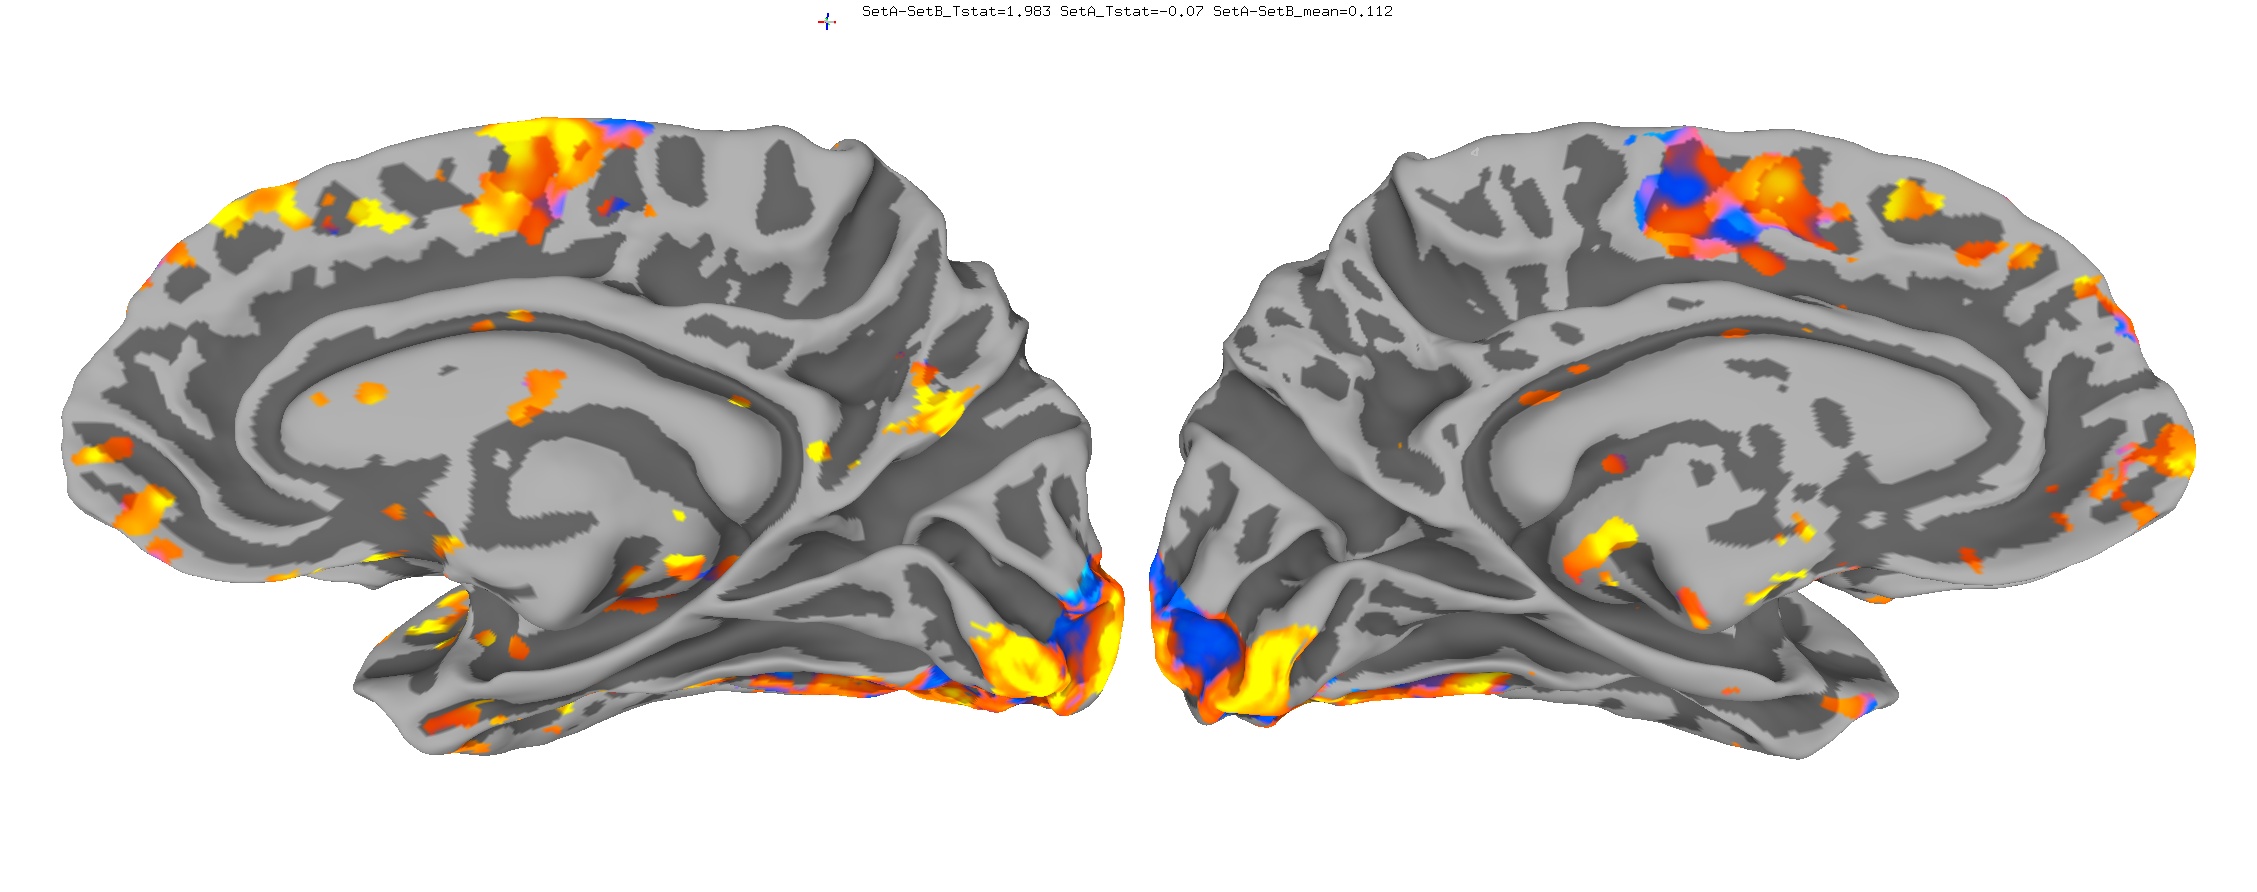

Functional Data

Functional data of the Mouth vs. Eye contrast mapped to the average surface. It is hard to quantify the difference, but one way is to compare the maximum statistical values; with better intersubject alignment, these would presumably increase.

- NEW: Max t-value for Mouth: 9.3 Eye:10.1 Eye vs Mouth: 5.6

- OLD: Max t-value for Mouth: 7.9 Eye:8.8 Eye vs Mouth: 5.8

New

Old